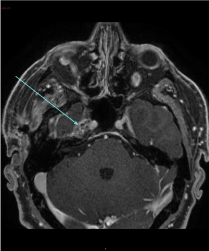

The MRI brain revealed a lesion involving the Meckel’s cave on the right side measuring 11 × 20 × 10 mm. It was isointense on the T1 weighted sequence, and relatively isointense on the T2 weighted sequence (Figure 2A) with loss of the normal signal of Meckel’s cave compared to the left side. The post-contrast T1 fat saturated sequence (Figure 2B) demonstrated heterogeneous enhancement of the lesion with punctate hypointense regions within the lesion. The lesion abutted the intracavernous component of the right internal carotid artery. Most of the abnormality involved the antero-superior cavernous sinus thereby obliterating the signal from the right Meckel’s cave. There was normal enhancement of the major intracranial vascular structures. There were no other intracranial space occupying lesions and there was no mass effect. There was no meningeal enhancement that would be suggestive of leptomeningeal disease. The ventricles and CSF spaces were normal.

Figure 2(A): MRI scan (T2 weighted coronal sequence) showing heterogeneous enhancement of the lesion in Meckel’s cave on the right side with punctate hypointense areas within the lesion.

Figure 2(B): Post contrast T1 fat saturated (axial sequence) showing a lesion measuring 11 × 20 × 10 mm demonstrating heterogeneous enhancement in Meckel’s cave on the right side.